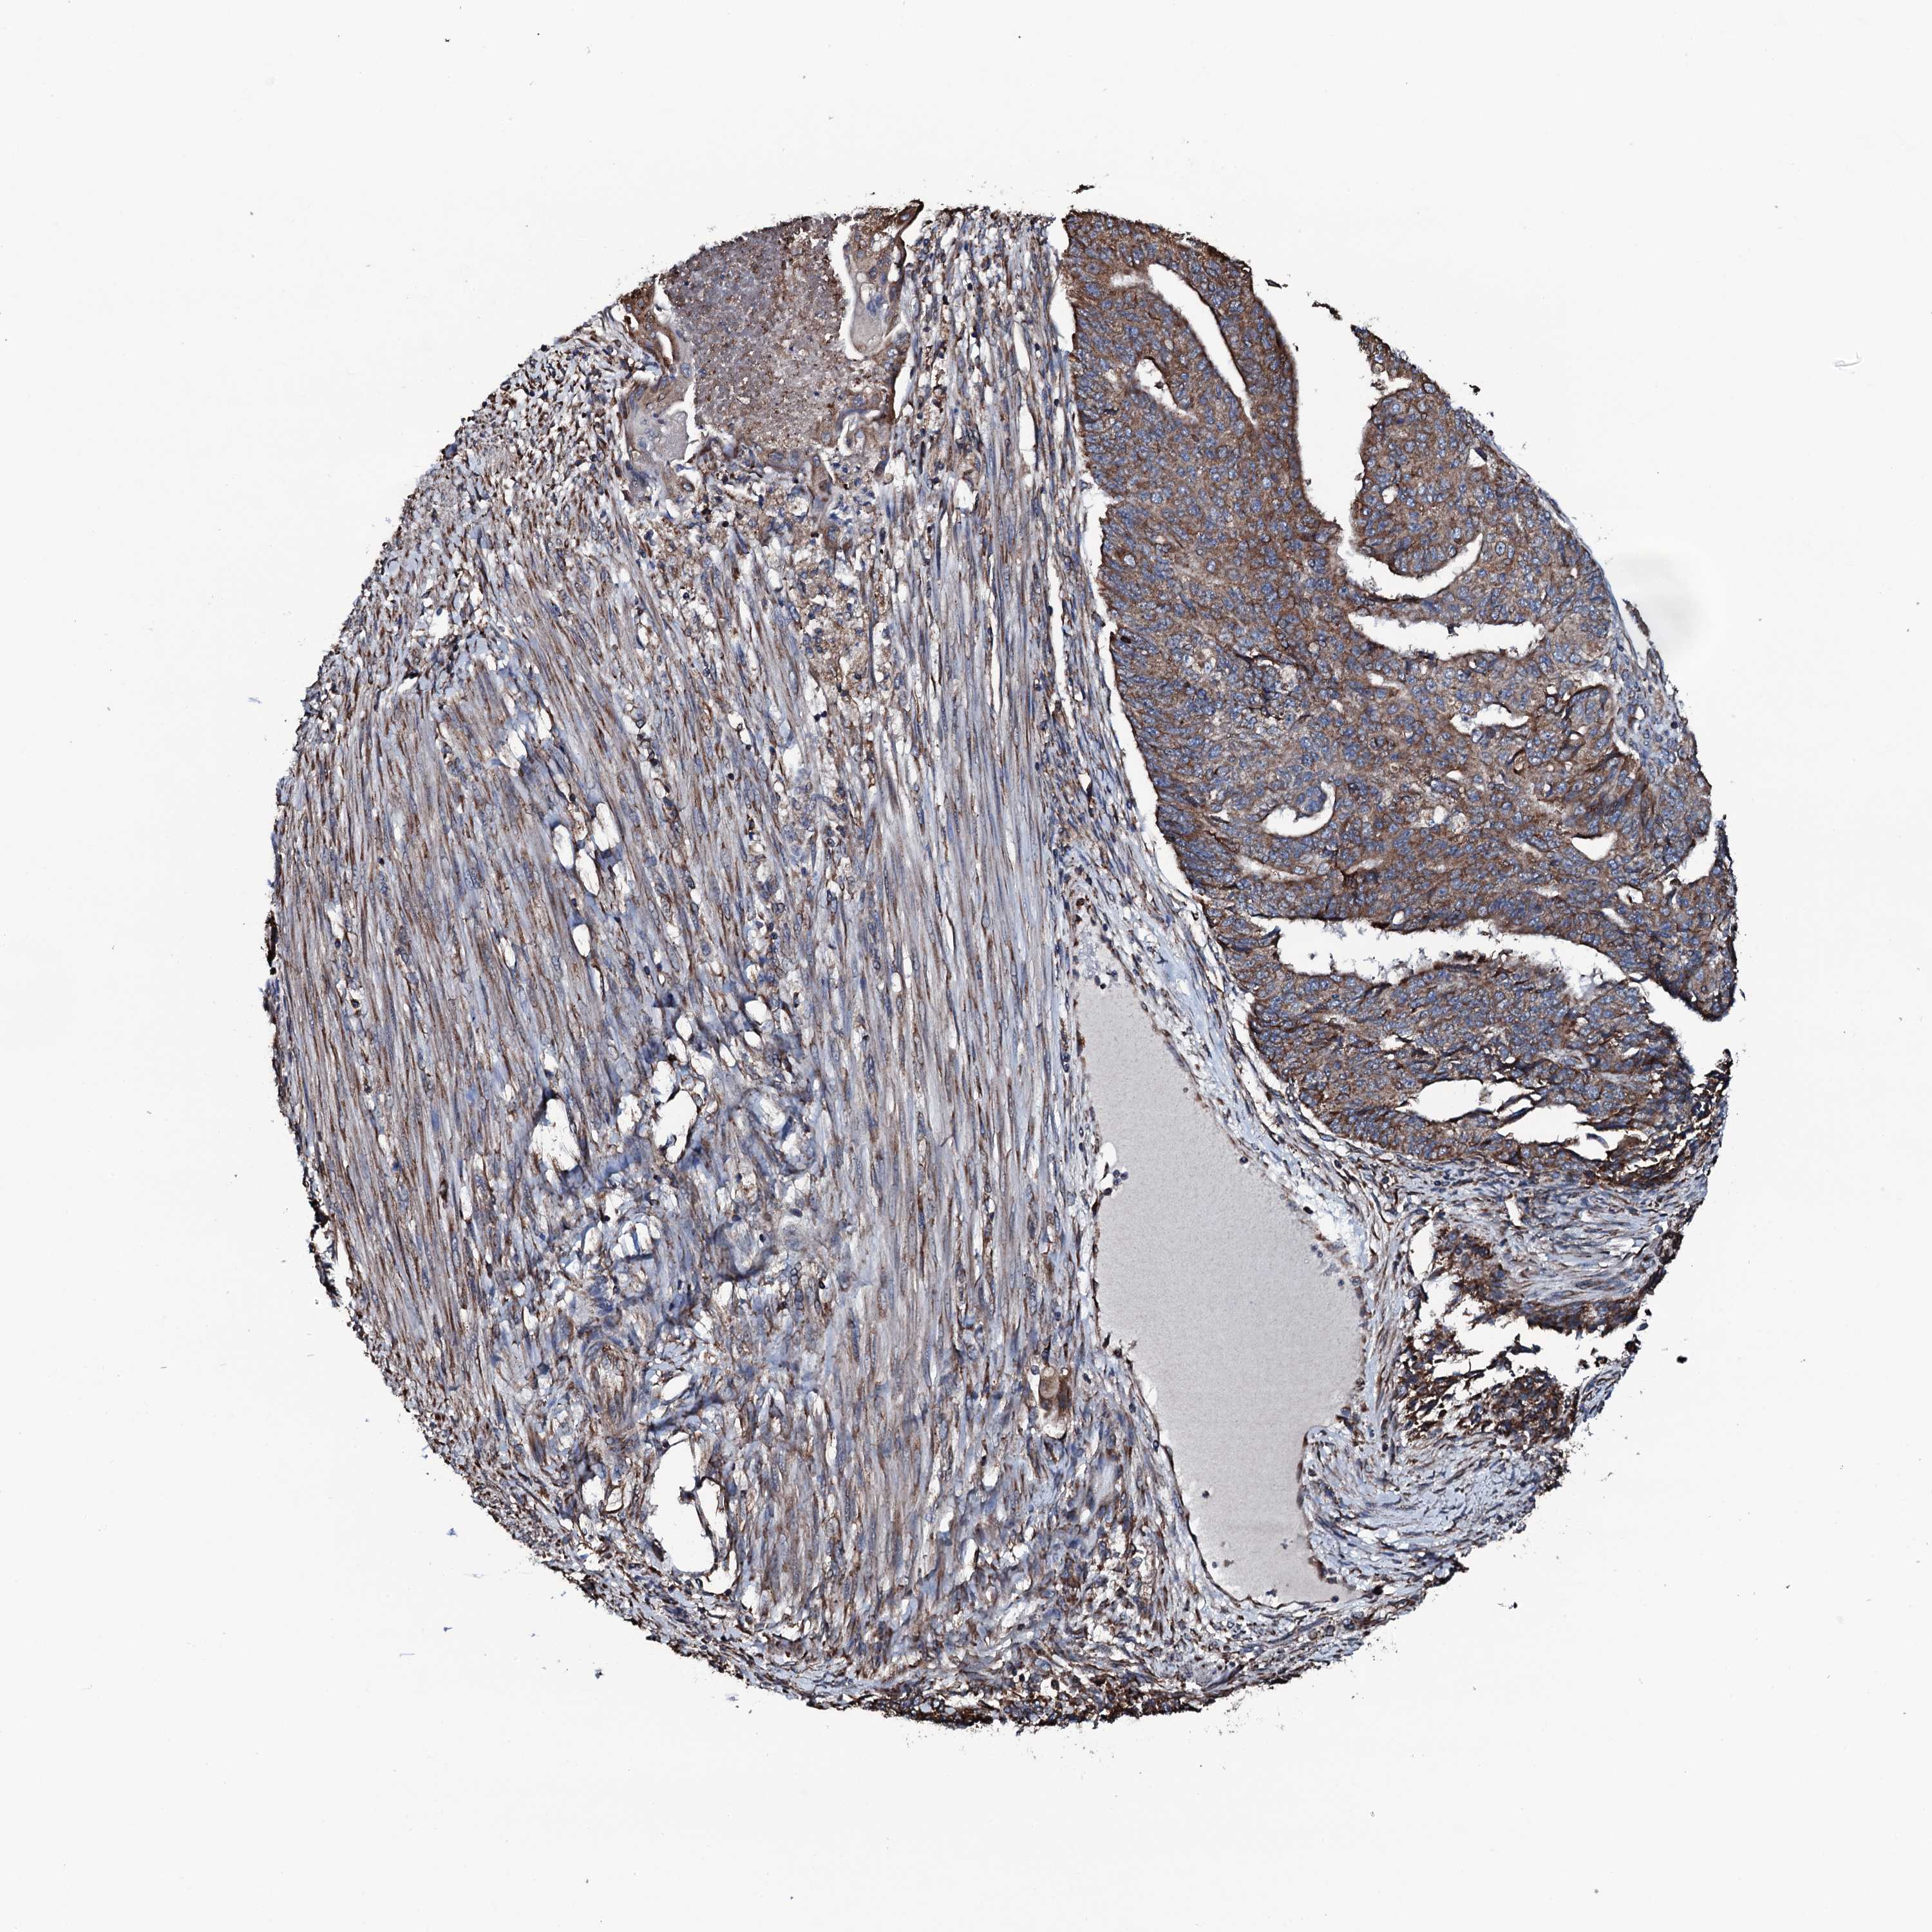

ENDOMETRIAL CANCER - Protein expressioni

A mouse-over function shows sample information and annotation data. Click on an image to view it in a full screen mode. Samples can be filtered based on level of antibody staining by selecting one or several of the following categories: high, medium, low and not detected. The assay and annotation is described here.

Note that samples used for immunohistochemistry by the Human Protein Atlas do not correspond to samples in the TCGA dataset.

Antibody stainingi

Antibody staining in the annotated cell types in the current human tissue is reported as not detected, low, medium, or high, based on conventional immunohistochemistry profiling in selected tissues. This score is based on the combination of the staining intensity and fraction of stained cells.

Each image is clickable and will lead to virtual microscopy that enables deeper exploration of all samples and also displays staining intensity scores, fraction scores and subcellular localization as well as patient and tissue information for each sample.

Antibody HPA040727

Staining

High

Medium

Low

Not detected

Intensity

Strong

Moderate

Weak

Negative

Quantity

>75%

75%-25%

<25%

None

Location

Nuclear

Cytoplasmic/membranous

Cytoplasmic/membranous,nuclear

Adenocarcinoma, NOS